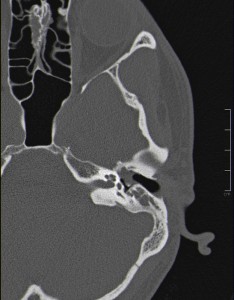

La opción correcta sería realizar al paciente un TC simple de cráneo con posterior reconstrucción coronal. Pues a parte de ser el TAC la prueba de elección para cualquier estudio de cráneo, lo es también para valorar las estructuras anatómicas del oído medio y descartar patología estructural en esta localización. Permite distinguir fácilmente los dos componentes principales del oído (hueso, de máxima densidad, y aire, de mínima densidad), así como las estructuras de densidad intermedia entre ambos, que se corresponderían con partes blandas (ej. tímpano, nervio facial, etc). La reconstrucción coronal en el oído permite un estudio más completo de la localización de las posibles alteraciones anatómicas debido a la complejidad estructural de este aparato.